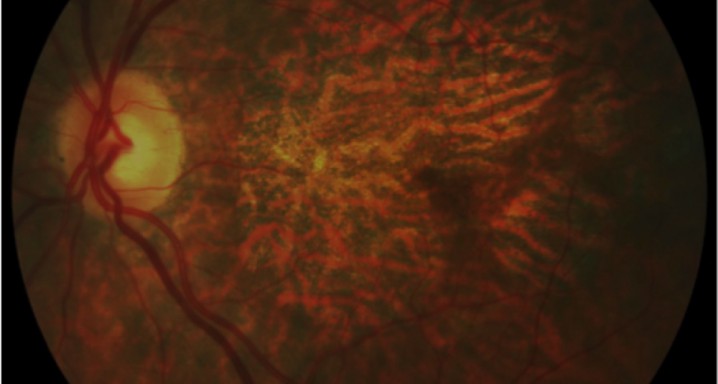

Transconjunctival sutureless vitrectomy with tissue plasminogen activator, gas and intravitreal bevacizumab in the management of predominantly hemorrhagic age-related macular degeneration. 26/03/2013

Purpose: To determine the efficacy and safety of treating predominantly hemorrhagic age-related macular degeneration (AMD) with transconjunctival sutureless vitrectomy (TSV), tissue plasminogen activator (tPA), sulphur hexafluoride (SF6), and intravitreal bevacizumab.

Methods: Retrospective study, consecutive case series. Patients with acute hemorrhagic AMD treated with 25- or 23-gauge TSV, subretinal or intravitreal tPA, fluid-air-SF6 exchange and intravitreal injection of bevacizumab. All operations were performed within the first 5 days after the start of symptoms, which consisted of visual acuity (VA) loss and central scotoma.

Results: Fifteen eyes from 15 patients were included. The patients’ mean age was 79.6 years, and the mean follow-up was 11.8 months. Five patients (33%) were receiving oral anticoagulant treatment. At baseline, the mean VA (logMAR values) was 1.5 (20/640 Snellen equivalent). At the last follow-up visit, the mean VA was 1.1 (20/250) (P < 0.0001; paired t-test). The submacular hemorrhage was successfully displaced in all the cases. Complications consisted of three cases of vitreous hemorrhage and a tear or the retinal pigment epithelium. Twelve cases (80%) did not require further treatment during the follow-up period.

Conclusion: A surgical approach with 25- or 23-gauge TSV, tPA, SF6 and intravitreal bevacizumab is an efficacious and safe procedure in patients with hemorrhagic AMD. Early treatment is advisable for obtaining the optimal outcome.